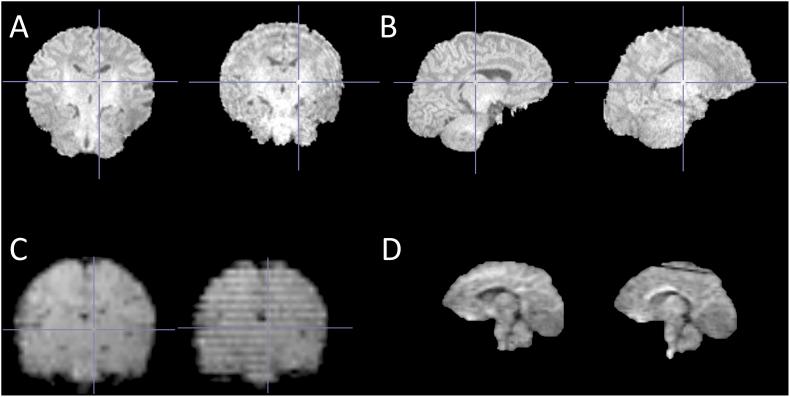

Magnetic resonance imaging (MRI) is a safe method to examine human brain. However, a typical MR scan is very sensitive to motion, and it requires the subject to lie still during the acquisition, which is a major challenge for pediatric scans. Consequently, in a clinical setting, sedation or general anesthesia is often used. In the research setting including healthy subjects anesthetics are not recommended for ethical reasons and potential longer-term harm. Here we review the methods used to prepare a child for an MRI scan, but also on the techniques and tools used during the scanning to enable a successful scan. Additionally, we critically evaluate how studies have reported the scanning procedure and success of scanning. We searched articles based on special subject headings from PubMed and identified 86 studies using brain MRI in healthy subjects between 0 and 6 years of age. Scan preparations expectedly depended on subject's age; infants and young children were scanned asleep after feeding and swaddling and older children were scanned awake. Comparing the efficiency of different procedures was difficult because of the heterogeneous reporting of the used methods and the success rates. Based on this review, we recommend more detailed reporting of scanning procedure to help find out which are the factors affecting the success of scanning. In the long term, this could help the research field to get high quality data, but also the clinical field to reduce the use of anesthetics. Finally, we introduce the protocol used in scanning 2 to 5-week-old infants in the FinnBrain Birth Cohort Study, and tips for calming neonates during the scans.